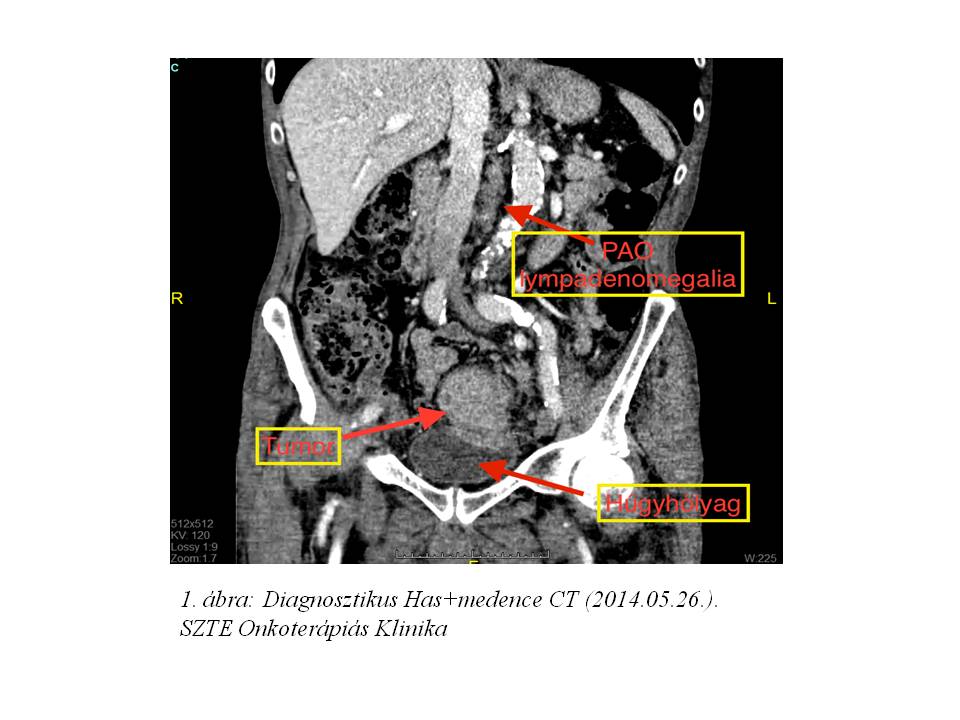

A szövettani mintavétel közepesen-jól differenciált adenocarcinomát igazolt. A képalkotó vizsgálatok alapján regionális, illetve PAO régióban detektálható lymphadenomegalia is igazolódott (1. ábra, 2. ábra).Stagingmellkas CT vizsgálat tüdőáttétet nem igazolt, tumor marker vizsgálatok minimális carcino-embrionalis antigén (CEA) emelkedést mutattak (4,74 M ng/ml, norm. tartomány‹4,70). Komplett kivizsgálás alapján a daganat iniciális stadiuma T4, N1 (LYM), M1 (PAO nyirokcsomó érintettség) lett definiálva, mely miatt, onkoteam döntés alapján, neoadjuváns kemoradioterápia indult 2014. júniusában (3. ábra, 4 ábra). A radioterápia indításától kezdve folyamatos compliance problémák nehezítették a kezelést. A beteg a szükséges kontrollvizsgálatokon nem vett részt, GI és vizeletürítési panaszaival SBO-n, sebészeti és urológiai ambulancián jelent meg, mely miatt sugárkezelését 11 frakció (19,8 Gy) leadását követően felfüggeszteni kényszerültünk. A beteg a sugárérzékenyítő, orális capecitabine (Coloxet, 825 mg/m2) citosztatikumot is csupán 1 hétig szedte. A fokozódó subileusos panaszok miatt urgens, székletpasszázst biztosító deviáló tranversostoma képzés történt SZTE Szebészeti Klinikán.